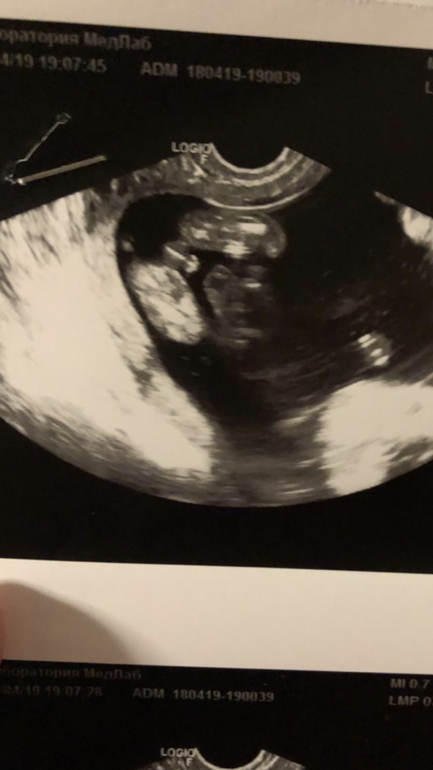

Как думаете тут пол уже без вариантов ?)

Вопросы про УЗИ, обследования и анализы: что, где, как, когда?В 12 недель говорили девочка

Сейчас 16/17

Мне не показывали узи монитор и не делали фото( Не знаю как выглядит девочка. Но примерно так у меня выглядел сын) Хороший такой перчик) Думаю, тут точно вряд ли девчуля

Да, мальчик без вариантов.. у девочек ничего подобного на таком сроке между ножек не торчит

вы хотя бы напишите, кого вам говорили. Для меня ничего не понятно. На первом будто мальчик